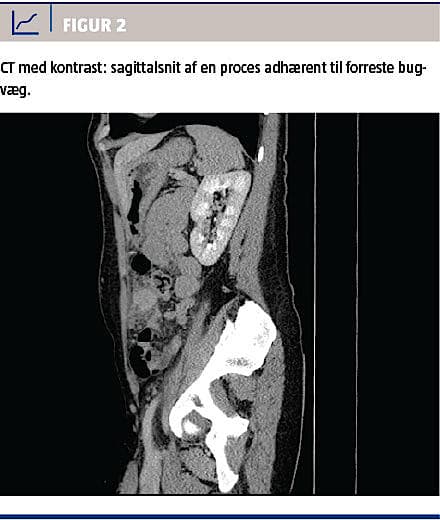

Ved en gynækologisk undersøgelse fandt man normale forhold med en spiral in situ. De vitale parametre var upåfaldende. En biokemisk undersøgelse viste normalt hæmoglobinniveau, basisk fosfatase og negativ S-humant choriongonadotropinniveau, men forhøjet C-reaktivt proteinniveau til 16 mg/l og alaninaminotransferaseniveau på 77 E/l. En CT af abdomen med i.v.-kontrast viste en atypisk inflammatorisk proces i venstre side af abdomen (Figur 1 og Figur 2), og der blev udført diagnostisk laparoskopi på mistanke om inflammeret Meckels divertikel. Ved laparoskopien fandt man i omentum majus en solid tumor, som var adhærent til forreste bugvæg. Efter at man havde sikret sig, at der i øvrigt var normale forhold intraabdominalt, blev tumoren laparoskopisk fjernet en bloc. Makroskopisk vurderet var tumoren 45 × 40 × 20 mm. På snitfladen var den fast heterogen med fedtvævslignende områder og nekroselignende forandringer centralt. Ved mikroskopi af omentet påvistes Actinomyces med karakteristiske sulphur granules bestående af bakterier og inflammatoriske celler (Figur 3). Dyrkning af ascitesvæske og podning fra IUD og cervix viste ingen vækst af Actinomyces. Efter konstatering af Actinomyces fik patienten fjernet spiralen og blev sat i i.v.-behandling med penicillin 5 mio. IE × 4 dagligt i 13 dage, efterfulgt af otte dages behandling med clindamycin 900 mg. Derefter blev patienten behandlet med amoxicillin 750 mg × 3 dagligt.

Abdominal aktinomykose kan give diagnostiske vanskeligheder, da symptomerne er ukarakteristiske og ofte opstår længe efter den udløsende årsag. Billeddiagnostik og laboratorieprøver er ligeledes uspecifikke, hvorfor symptomerne ofte tolkes som hidrørende fra en malign tumor [3]. Ved abdominal aktinomykose har præoperativ diagnostik uden biopsi en succesrate på op til 10% [3]. CT fører ofte til kirurgisk indgreb pga. tumormistanke.